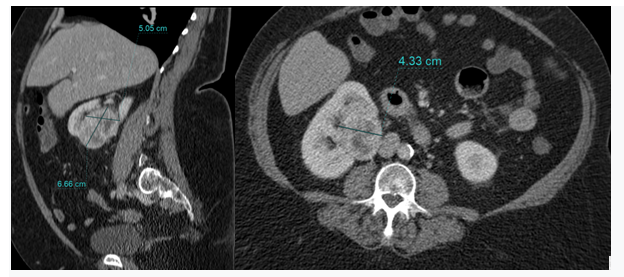

Tumor to Tumor: Metastatic Lobular Breast Carcinoma into Primary Clear Cell Renal Cell Carcinoma